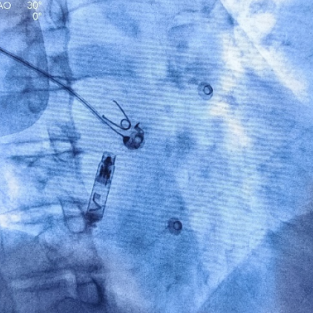

心房无导线起搏器最终植入位置

手术首先利用电生理四极导管标测Bachmann束区域,留影做参考;再次利用保护套筒造影精准确认植入位置,后退保护套筒,将心房无导线旋入1.5圈,参数良好且稳定。

自身:P波宽度96ms,PR间期215ms

Bachmann束区域起搏:P波宽度75ms,PR间期185ms